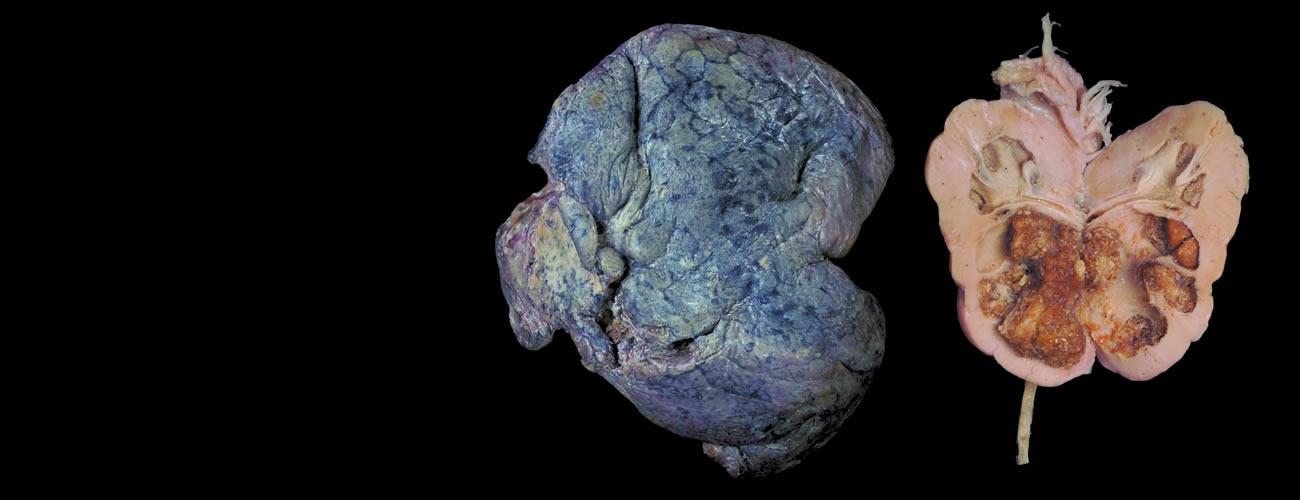

病理学标本

包括大体和玻片标本,展示疾病所致人体器官组织的病理变化特征,其中大部分是目前很难或根本无法收集到的标本。